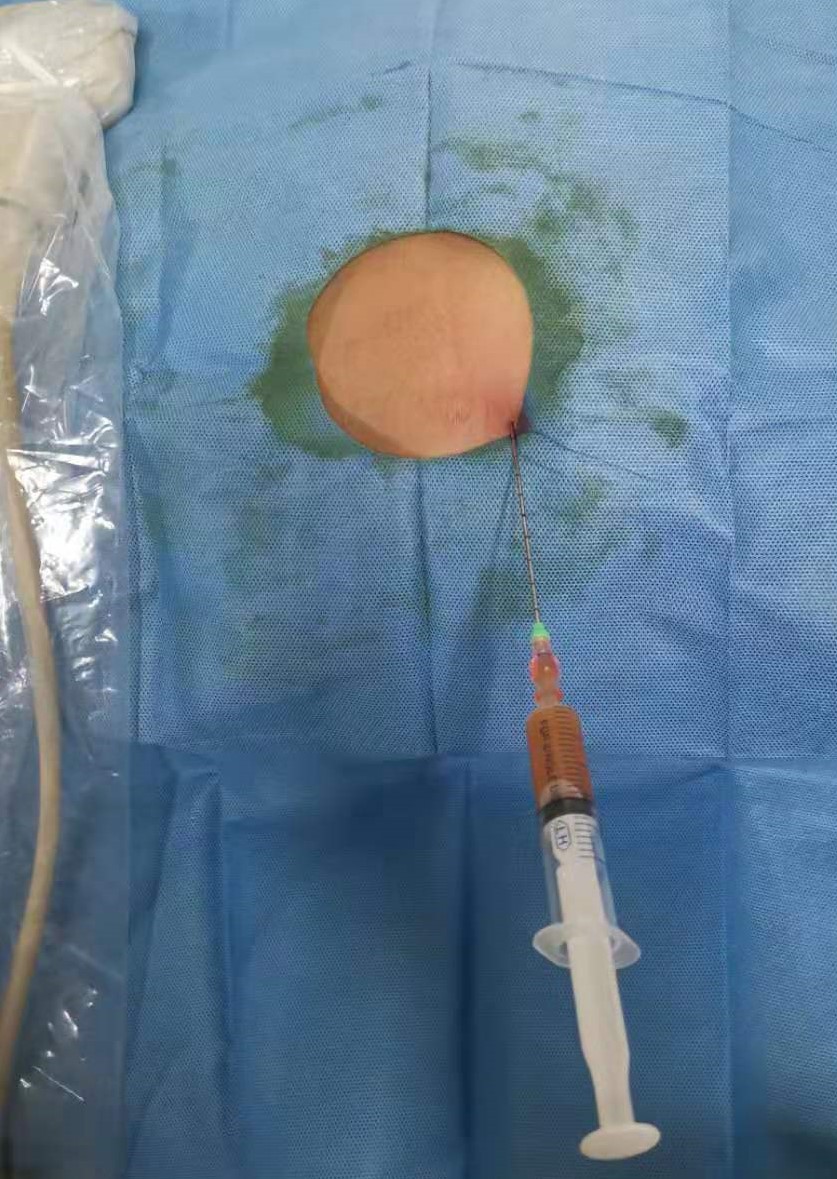

患者取俯卧位,充分暴露手术野,经臀超声扫查了解骶前脓肿情况,确定穿刺点,设计好穿刺路径。常规消毒铺巾,局麻,无菌保护套隔离探头。超声引导下PTC针穿刺直至脓腔边缘,迅速突破囊壁进入脓腔中心(图 3),退出针芯,外接注射器抽吸,见脓液流出(图 4)。将导丝通过针管插入脓腔,固定导丝,拔出针管,刀片沿导丝在臀部做2~3 mm小切口。插入扩张管扩张针道,经导丝将猪尾导管联合支撑管插入脓腔,超声确认穿刺到位(图 5)。拔出导丝,试抽有脓液流出,前推猪尾导管至其前端带侧孔段全部进入脓腔,拔出支撑管,可见液体流出。拉紧导管末端细线使导管尾端呈环状并固定,再次超声检查确定引流管在脓腔内(图 6),用缝线将引流管固定于皮肤上(图 7)。抽出约120 mL脓性液体,生理盐水反复冲洗脓腔,外接无菌引流袋。抽出的脓液取样送细菌培养,并做药物敏感实验。

|

| 图 3 超声引导下PTC针破壁进入脓腔 |

| 图 4 试抽出脓液 |